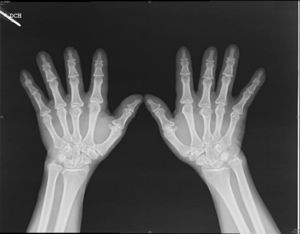

Caso clínicoVarón de 59 años con antecedente personal de diabetes mellitus tipo 2 en tratamiento con antidiabéticos orales, que acude a consulta de Reumatología por dolor inguinal bilateral y dorsolumbalgia de intensidad dolorosa progresiva, ambos de ritmo mecánico, que el paciente califica de muy intenso y que desencadenan dificultad progresiva para la deambulación; y por episodios de disnea de moderados esfuerzos, cuyo origen, estudiado por Neumología, era debido a dificultades en la expansión torácica. El cuadro doloroso no había presentado una respuesta satisfactoria a antiinflamatorios no esteroideos ni a opiáceos menores. En la exploración física se observa talla de 146cm, marcada cifosis dorsal, obesidad troncular, limitación importante para la flexoextensión y las rotaciones de ambas articulaciones coxofemorales, y braquidactilia en ambas manos. Hemograma y bioquímica sanguínea con valores normales. El estudio radiológico convencional de columna dorsolumbar, anteroposterior de pelvis y posteroanterior de manos se muestran en las figuras 1 a 4.

El paciente descrito presenta datos que sugieren una displasia espondiloepifisiaria tarda. Esta entidad tiene una herencia recesiva ligada al cromosoma X1, estando por lo tanto afectados sólo los varones. Se han descrito mutaciones en el gen SELD en el cromosoma Xp22.12-p 23.311. El diagnóstico se realiza entre los 5 y los 10 años de edad, cursando con enanismo de tronco corto; esto es, retraso en el crecimiento de la columna vertebral con una talla media final de 145cm y desproporción entre la longitud de las extremidades y el tronco2,3. La articulación coxofemoral está siempre afectada en coxa vara con aplanamiento leve de las epífisis, que conducen a cambios artrósicos precoces, y que pueden, en estadios más avanzados, incapacitar al paciente2–4. A nivel axial se describen cambios displásicos vertebrales con platiespondilia, que provocan cifosis progresiva4–6 con aumento del diámetro anteroposterior del tórax, y que en último término puede provocar episodios de disnea. No aparece retraso mental, se han descrito formas familiares con asociación a condrocalcinosis7,8 y existe una forma de displasia espondiloepifisiaria tarda asociada a artropatía degenerativa precoz, que puede simular artritis reumatoide juvenil9.